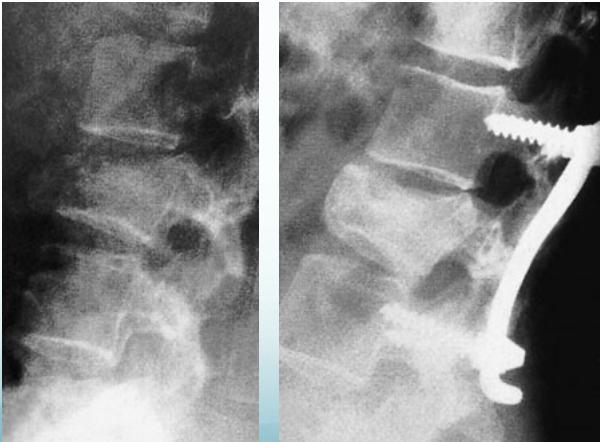

Burst Injury L-Spine

- Axial compression: shattered vertebral body

- Posterior fragments into spinal canal

- Usually unstable

- CT required

Burst Injury Classification

Is this a compression or a burst fracture?

- A burst fracture

- Why?

- Posterior displacement

Neurological Injuries